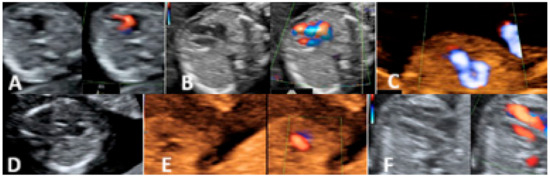

2.2. Second Trimester Scanning and Sections

3.2. Second-Trimester Evaluation